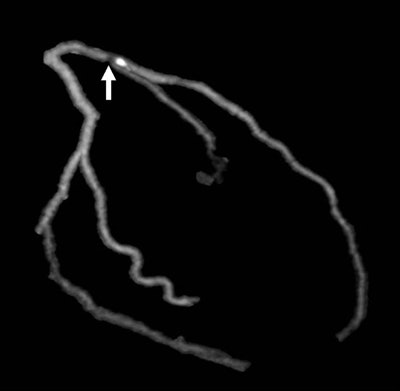

| Images 1-7 shown top to bottom: A 59-year-old man presented with atypical chest pain. A circumscribed, short-segment high-degree stenosis (arrow) in the proximal LAD is difficult to detect on transverse (1), sagittal (2), or coronal (3) multiplanar reformats. Use of advanced visualization tools with automated extraction of the coronary artery tree (4) and automated display as curved multiplanar reformat (5) clearly identifies the lesion, also seen in the 3D view (6) and confirmed on conventional catheter angiography (7). All images courtesy of Dr. U. Joseph Schoepf. |